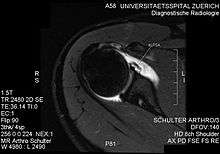

ALPSA lesion

An ALPSA (anterior labral periosteal sleeve avulsion) lesion is an injury at the front of the shoulder associated with shoulder dislocation.